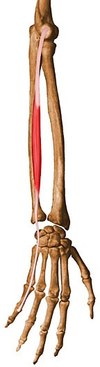

Extensor Pollicis Longus and Brevis

Longus

Origin: Posterior surface of middle 1/3 of ulna and interosseous membrane

Insertion: Base of distal phalanx of thumb

Action: Extends distal phalanx of thumb at carpometacarpal and interphalangeal joints

Innervation: Posterior interosseous nerve (C7 and C8), the continuation of the deep branch of the radial nerve

Arterial Supply: Posterior interosseous artery